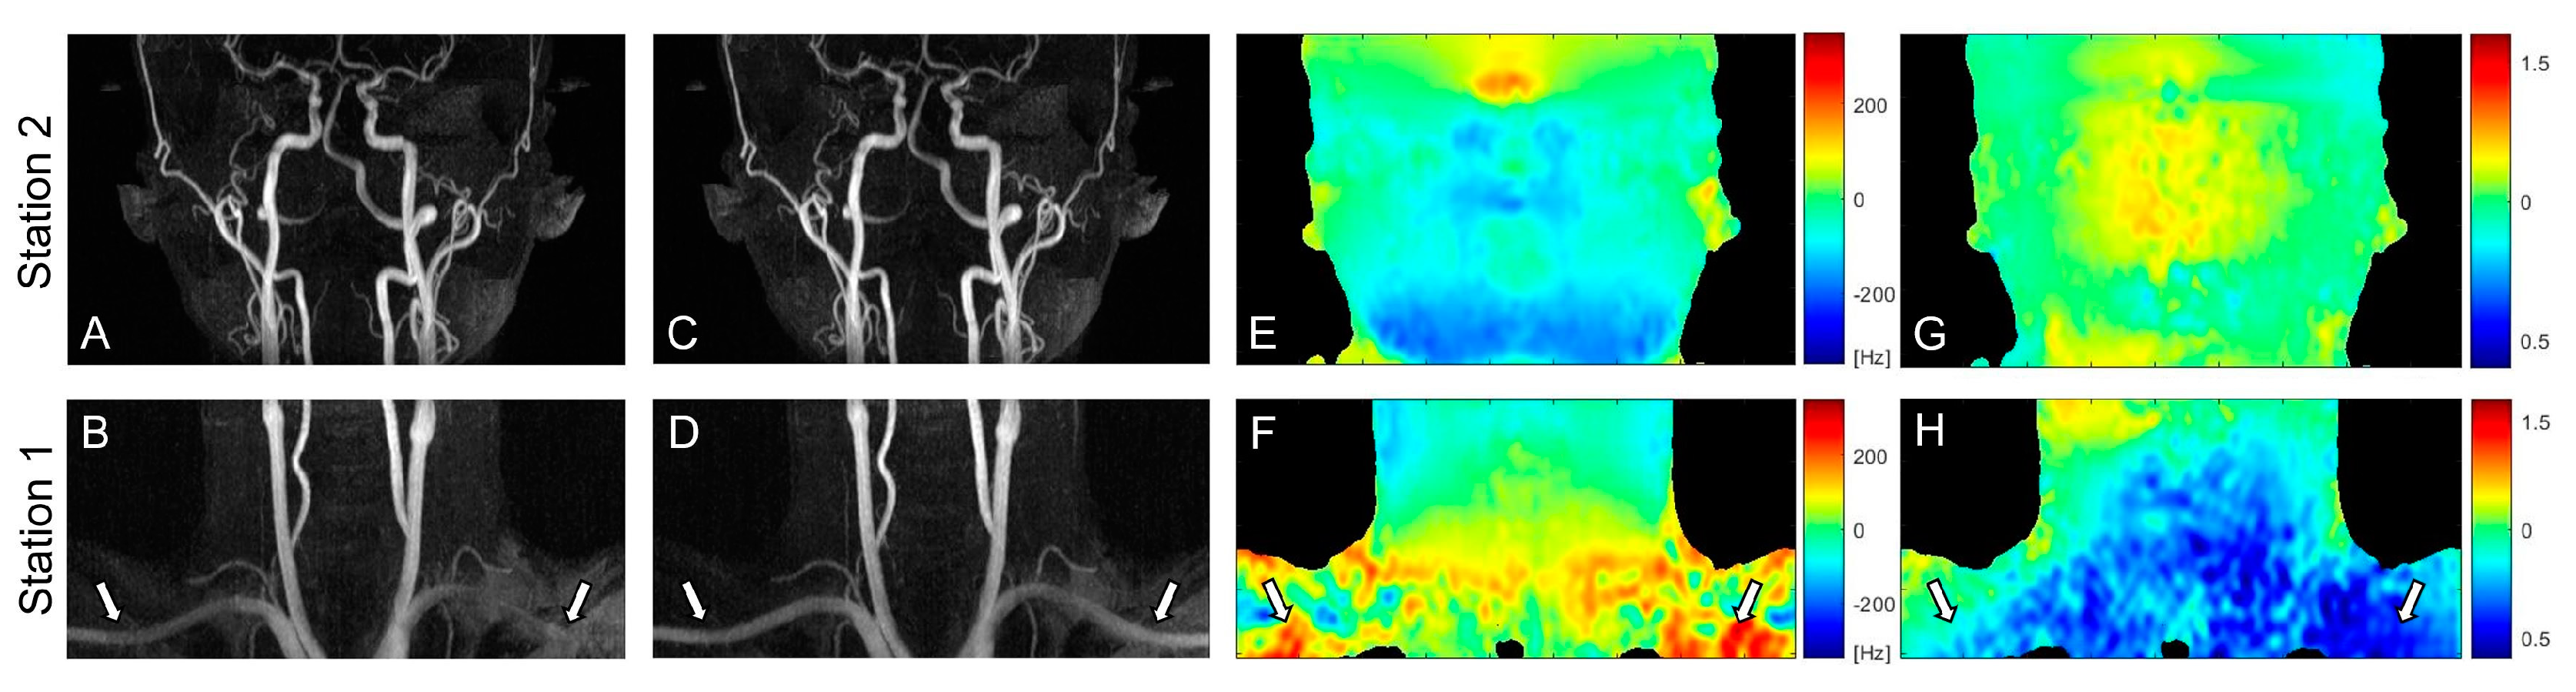

3.1. PC Flow and Field Mappings